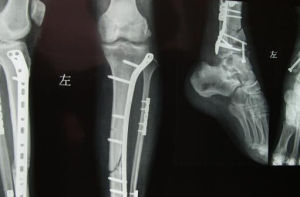

骨筋膜室綜合徵一經確診,應立即切開筋膜減壓。早期徹底切開筋膜減壓是防止肌肉和神經發生缺血性壞死的惟一有效方法。切不可等到出現5“P”體徵後才行切開減壓術,從而導致不可逆的缺血性肌攣縮。切開的皮膚一般多因張力過大而不能縫合。可用凡士林紗布松松填塞,外用無菌敷料包好,待消腫後行延期縫合,或套用游離皮片移植閉合傷口。切不可勉強縫合皮膚,失去切開減壓的作用。